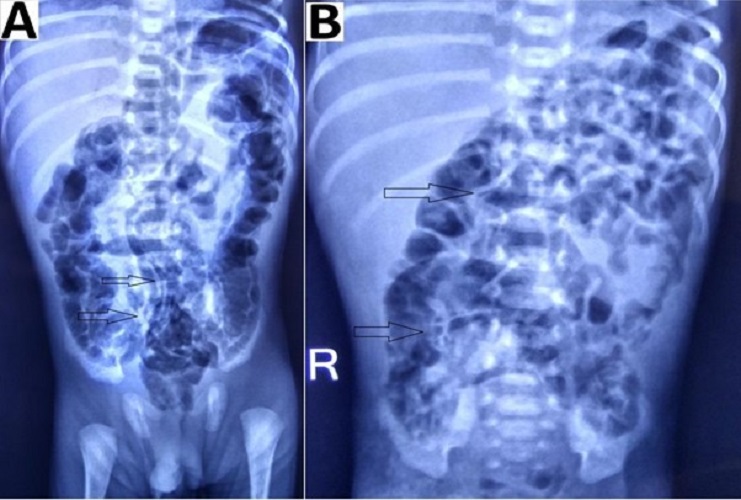

Figure 3

Preoperative radiographs showing: (A) dilated bowel loops (red arrow) at the left upper abdomen and (B) fixed dilated bowel loops (red arrow) at an interval of 24 hours.

In patients with suspected NEC, a radiological evaluation can confirm the staging as proven or advanced.[2], [15], [16] Extraluminal air (free air) is the sole radiologic finding that is considered as direct evidence of perforation and has been accepted widely as an indication for surgery.[17] In suspicious cases, abdominocentesis can be performed to ascertain the peritoneal contents and confirming the presence of free air.[18] As per our study, pneumoperitoneum was the indication for surgery in 69% of patients, a proportion that was greater than those reported by other studies.[19], [20], [21] Indications for surgery in one of the studies were clinical deterioration (37%), presence of abdominal mass(15%), and positive peritoneal tap (5%). In the absence of pneumoperitoneum, we considered surgery in 31% (16/51) patients based on clinical deterioration, metabolic derangement, features of intestinal obstruction i.e. fixed dilated bowel loops (Fig. 3), transient thickening of the intestinal wall (Fig. 4). In group B, during surgery, 11/16 (69%) had actual perforation, even in the absence of pneumoperitoneum. Similar criteria were taken up by Villamil et al; in their study, intraoperative perforation was seen in 39% of the patients with no radiological pneumoperitoneum. [20]

Intestinal distension, often secondary to obstruction, is the most common sign visible in 90% of radiograms in neonates with NEC.[2] Although no evidence-based guidelines are available regarding the duration and frequency of radiographic examination, an attempt was made by Coursey et al. in 2009 using a ten-point scale for abnormal radiographic findings in infants with clinically suspected NEC.[24] They called it Duke’s Abdominal Assessment Scale (DAAS score). Findings of fixed (unchanging) bowel loops, definite pneumatosis, or portal venous gas as revealed by DAAS scores of 7, 8, or 9 were highly associated with eventual surgical intervention for suspected NEC.[25] Bowel wall thickening from oedema and haemorrhage is seen as separated bowel loops on radiographs. [15] Increased bowel wall thickening on radiographs in presence of clinical features is an early sign of NEC (Fig. 4). A wall thickness greater than 2.6 mm is a pathological finding on ultrasound. [21]

We detected fixed bowel loops in 3 patients (18%) pneumatosis intestinalis (Fig. 5) in 1 (6%), portal venous gas in 1 (6%), and massive ascites (Fig. 4) in 2 patients (12%) among the group B (with the absence of pneumoperitoneum). These percentages (findings) were relatively small in our study, but in presence of clinical signs, they contributed towards deciding to operate in our study. Thus collectively (clinico-radiologically), more than one sign according to Modified Bell’s staging was present in group B patients, i.e. 8 (50%) stage IIIA, 12 (75%) stage IIB, 1 (6%) stage IIA and 3 (18%) stage IA/IB.